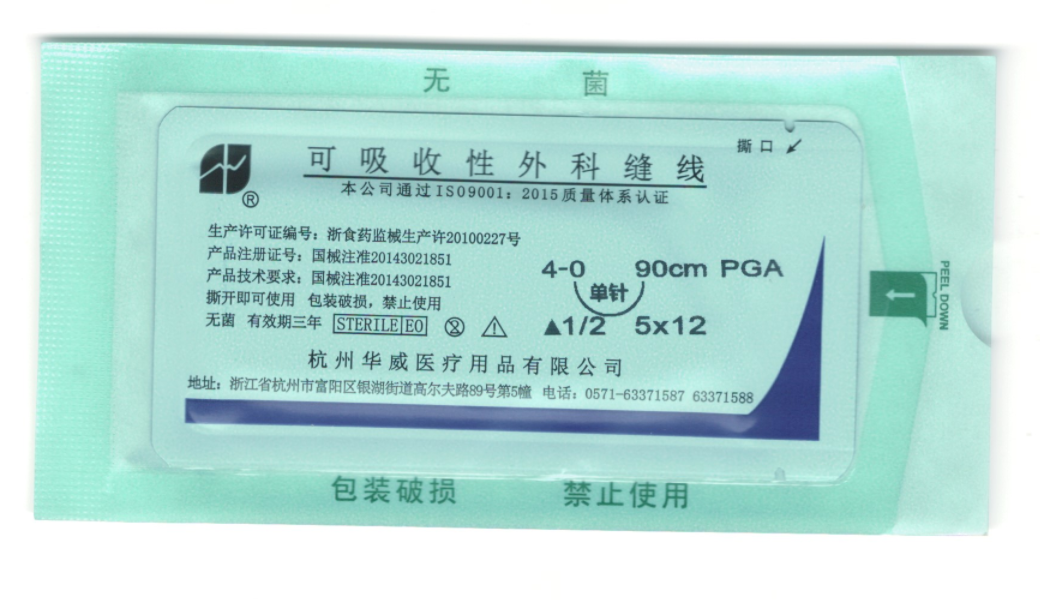

可吸收性外科縫線

公司主要生產經營各種醫用縫合針,醫用縫合線,手術刀片,醫用內窺鏡,微創手術器械等系列產品。產品規格齊、品種全,廣泛應用于普外科、整形外科、顯微外科、五官科、肛腸科、婦科、骨科、泌尿科、胸科、腦科等手術領域。產品暢銷全國20多省市并遠銷全球多個國家和地區,深受海內外客戶的贊譽。華威生產經營有20多年的歷史,全國擁有近1000家客戶。